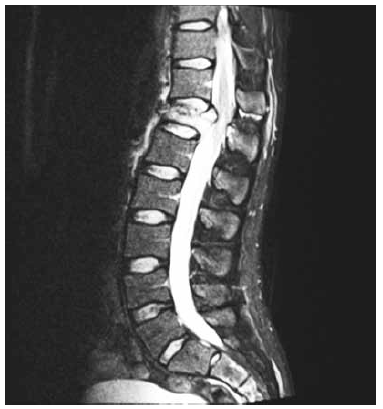

Paciente vítima de queda de moto com capacete, relatando fortes dores em região dorsal, sem deficits motores nem sensitivos ao exame clínico. Em investigação radiológica com tomografia e ressonância identificou-se fratura de corpo de T12 tipo compressão com comprometimento de muro posterior, lesão de ligamentos interespinhosos e supraespinhosos entre T11 e T12, conforme imagem a seguir.

Qual a melhor conduta conforme preconizado por escore TLICS?